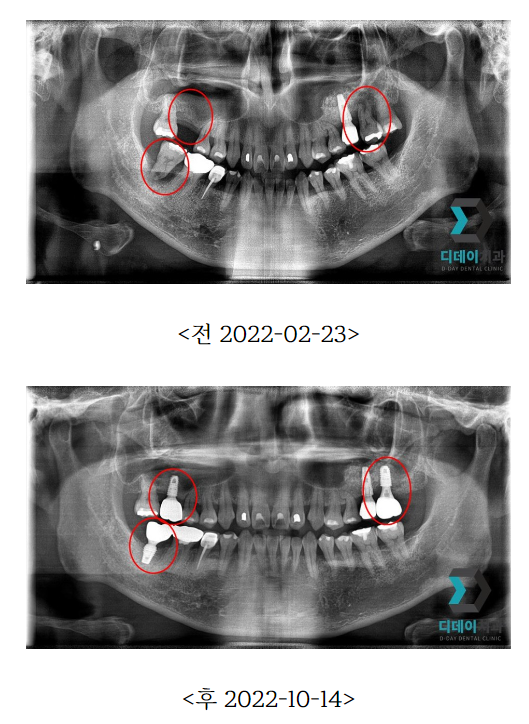

임 플 란 트가 필요할 정도로 구강 상태가 심각하다면 X-ray, 3D CT 등의 정밀검사를 통해

환 자분의 특징을 면밀히 파악하고 치 료를

계획해야합니다.

| 본 게시물은 의료광고법 제56조 1항을 준수하여, 의료 정보 제공 및 병원 홍보를 목적으로 디데이치과의원에서 직접 작성하였습니다.다만, 블로그에서 제공해 드리는 정보는 참조용으로만 활용하시고, 정확한 개인의 증상 파악은 의료기관에 직접 내방하시어 의료진을 통해 확인하실 것을 권유 드립니다.치과에서 진행되는 모든 시술 및 수술은 개인에 따라 부작용 (염증, 출혈, 부기, 신경 손상 등) 가능성이 있습니다. 따라서 사전에 의료진과 충분한 상담을 통해 결정하시길 바랍니다.게시물의 치료 사진은 실제 본원에서 모든 치료 과정을 마친 환자분의 동의하에 촬영되었습니다. 전후 사진은 동일인이며, 동일 조건하에 촬영되었음을 밝힙니다. |